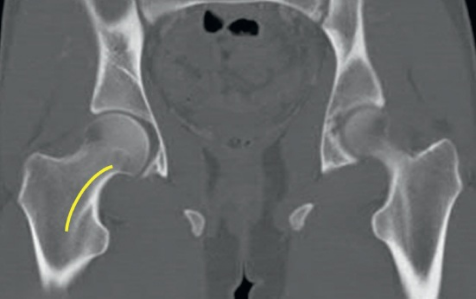

股骨距(calcar femorale)是股骨近端内部的一块致密垂直骨板(图1和图2中的黄色线标示部分)。该结构起自股骨干后内侧(小转子下方),向外侧穿过松质骨延伸至大转子。从临床角度看,此处的骨皮质增厚区域有助于抵抗内侧压缩负荷。股骨距的完整性对于区分稳定型与不稳定型骨折模式具有重要临床意义。该区域也是内植入物与骨组织产生最大抗变形力的关键接触部位。

什么是c型臂术中透视骨科精读 | 股骨近端骨折的转子区域与矢状面力线术中透视技巧_https://www.jmylbn.com_新闻资讯_第1张

图1

什么是c型臂术中透视骨科精读 | 股骨近端骨折的转子区域与矢状面力线术中透视技巧_https://www.jmylbn.com_新闻资讯_第2张

图2